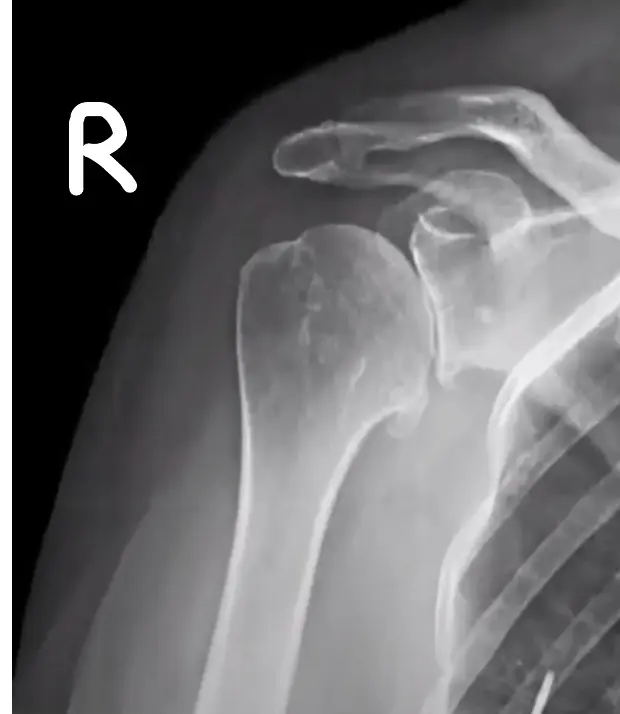

Injection of shoulder

This patient has chronic shoulder pain (OA glenohumeral / subacromial pathology) has not responded to NSAIDs. You are required to inject the site with steroid and local anesthetic agent.

| Indication of arthrocentesis of the shoulder | Diagnostic: arthritis, septic |

| Therapeutic: reducing massive effusion | |

| Steroid Injection for : OA glenohumeral joint, AC joint, sub- acromial bursa | |

| For Glenohumeral joint: | |

o Feel the coracoid, go lateral to it from anterior![]() ![]() Posterior glenohumeral injection | |